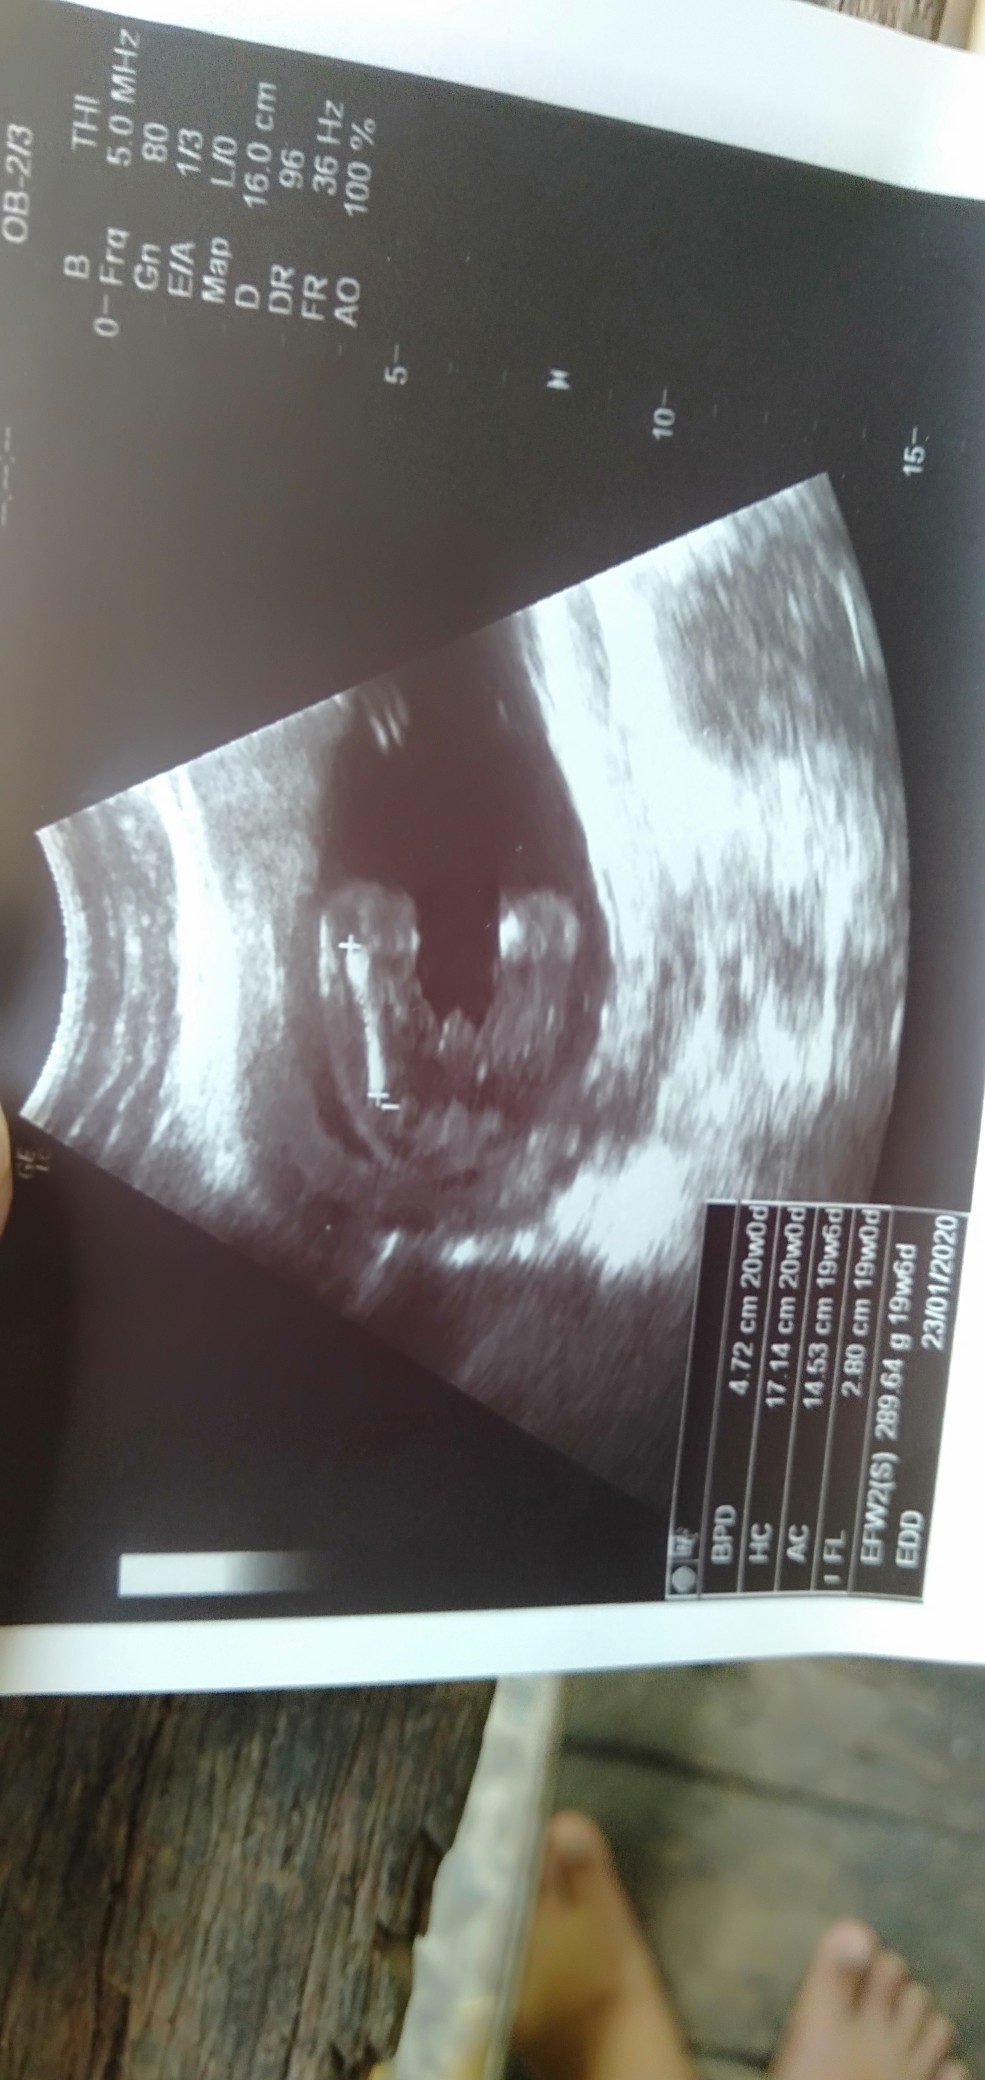

หญิงจ้า